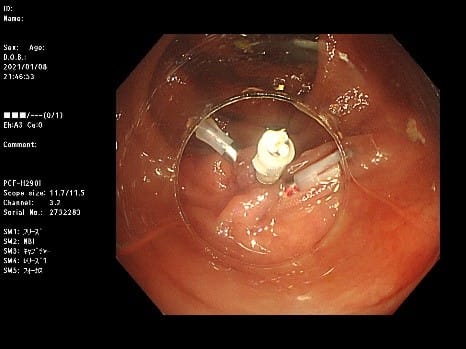

早期胃がんに対するESD(内視鏡的粘膜下層剥離術)

早期胃癌(▲)に対して内視鏡的粘膜下層剥離術(ESD)を行います。

色素を撒いて病変をわかりやすくします。